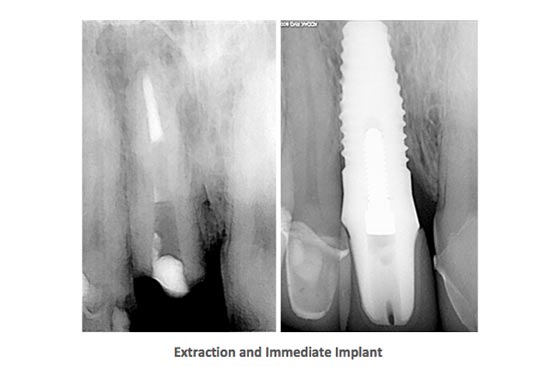

- Dental Implants